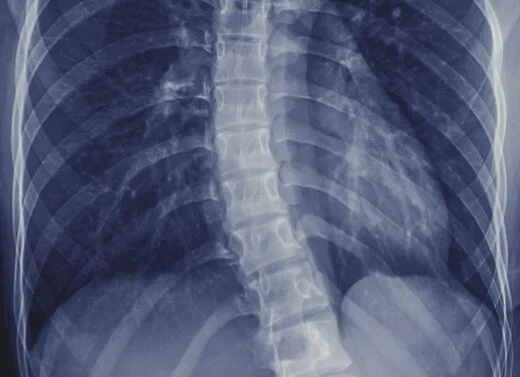

Welche sportarten bei skoliose vermeiden. Es gibt keine gesicherten Hinweise dafür dass bei vorbestehender Skoliose bestimmte Sportarten zu einer Zunahme der Deformität führen. Sportarten bei denen die Wirbelsäule großen Stoßbelastungen ausgesetzt ist sollten vermieden werden. Einige Skoliotiker bekommen Schmerzen bei starker Belastung da muss man auch ausprobieren was dir da gut tut und was nicht.

Bei Kindern und Jugendlichen ist eine Befreiung vom Schulsport bei leichten und mittelschweren Skoliosen nicht angezeigt. Bei Skoliosen bis zu 40 Grad sind generell alle Sportarten möglich und die aktive Teilnahme am Schulsport wird unbedingt empfohlen. Dies kann man mit einfachen Hantelübungen oder sogar ohne Gewichte durchführen.

Bezüglich der Neigung zu einem Rundrücken sind alle Sportarten geeignet die dafür sorgen dass Sie Ihr Atemvolumen steigern also Ausdauersportarten wie Rudern Schwimmen Radfahren. Sportarten bei denen die Wirbelsäule stark belastet wird wie beispielsweise Squash oder Kunstturnen sollten vermieden werden.